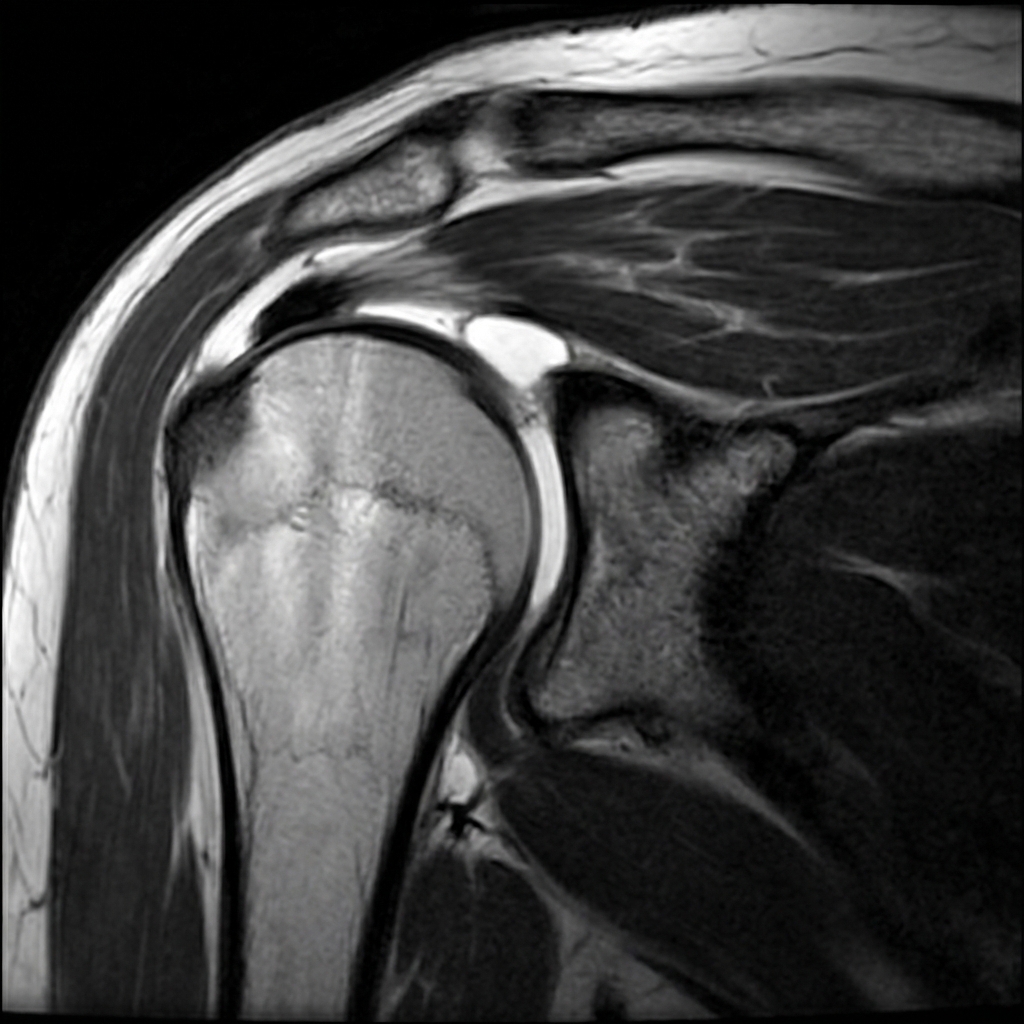

Clinical image for Rotator Cuff Tears

Source: AI-Generated: Educational MRI of Grade 3 Rotator Cuff Tear • OrthoVellum AI • OrthoVellum Educational Use

Describe the imaging findings that determine reparability of a rotator cuff tear. What classification systems are used?